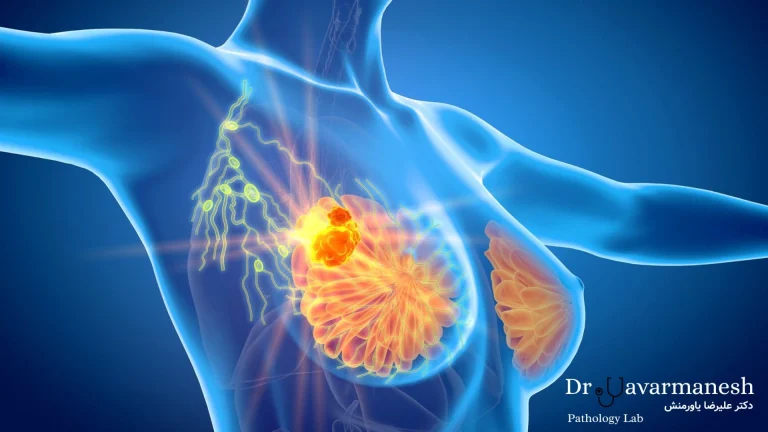

این نوع از سرطان، یکی از شایعترین انواع سرطان در میان زنان است و میتواند در هر سنی، حتی زیر ۳۰ سال یا در سنین بالا بروز کند. این بیماری معمولاً از بافت مجاری شیری یا غدد پستانی آغاز میشود و در صورت عدم تشخیص بهموقع، ممکن است به مرحله دوم، سوم یا حتی متاستاز در اندامهای دیگر برسد.

مکانیزمهای سلولی و مولکولی

این بیماری زمانی آغاز میشود که تعادل تقسیم سلولها بههم بخورد. جهشهای ژنی باعث رشد تودههای بدخیم پستان میشوند. در مراحل پیشرفته، ممکن است تومور به بافتهای اطراف یا اندامهای دیگر گسترش یابد.

اگر درمان نشود، ممکن است در آینده به نوع تهاجمیتر (IDC) تبدیل شود. - کارسینوم مجرای تهاجمی (IDC):

شایعترین نوع اومور پستان است و حدود ۷۰ تا ۸۰ درصد موارد را تشکیل میدهد.

در این نوع، سلولهای سرطانی از مجاری شیردهی خارج شده و به بافت اطراف پستان نفوذ میکنند.

در مراحل پیشرفتهتر، میتواند از طریق خون یا سیستم لنفاوی به سایر اندامها گسترش یابد. - کارسینوم لوبولار تهاجمی (ILC):

در مراحل پیشرفته، سرطان ممکن است به اندامهای دیگر گسترش پیدا کند (متاستاز).

به این نوع، سرطان سینهی متاستاتیک گفته میشود.